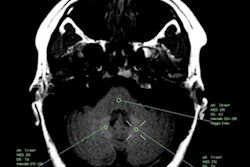

MR images of a 40-year-old woman with osteosarcoma who received 20 single doses of gadobutrol between 2007 and 2017. Transverse native T1-weighted spin-echo MR images (A, C) and corresponding transverse color-coded multiplanar reconstructions (B, D) of T1 maps. Images courtesy of Radiology.While more research is needed to draw a definitive conclusion between T1 relaxation times and gadolinium deposition, the results "support the concept that patients should be informed about the possibility of subclinical gadobutrol brain retention before undergoing contrast agent-enhanced MRI," the authors wrote.

All 220 subjects underwent unenhanced MRI brain scans on a 1.5-tesla MRI scanner (Magnetom Aera, Siemens Healthineers). The protocol included T1-weighted spin-echo and T1 and T2 mapping to determine visual signal-intensity changes; signal-intensity ratios of the globus pallidus to the thalamus and the dentate nucleus to the pons; and T1 and T2 relaxation times. In MRI terms, relaxation refers to how signals can weaken or broaden over time. T1 mapping helps calculate the loss of signal, while T2 mapping conveys broadening of the signal.

However, there were significantly shorter T1 relaxation times in the globus pallidus among patients with normal renal function and multiple administrations of gadobutrol, compared with control subjects with normal renal function. The difference between the two groups was 226.2 msec (p = 0.002).